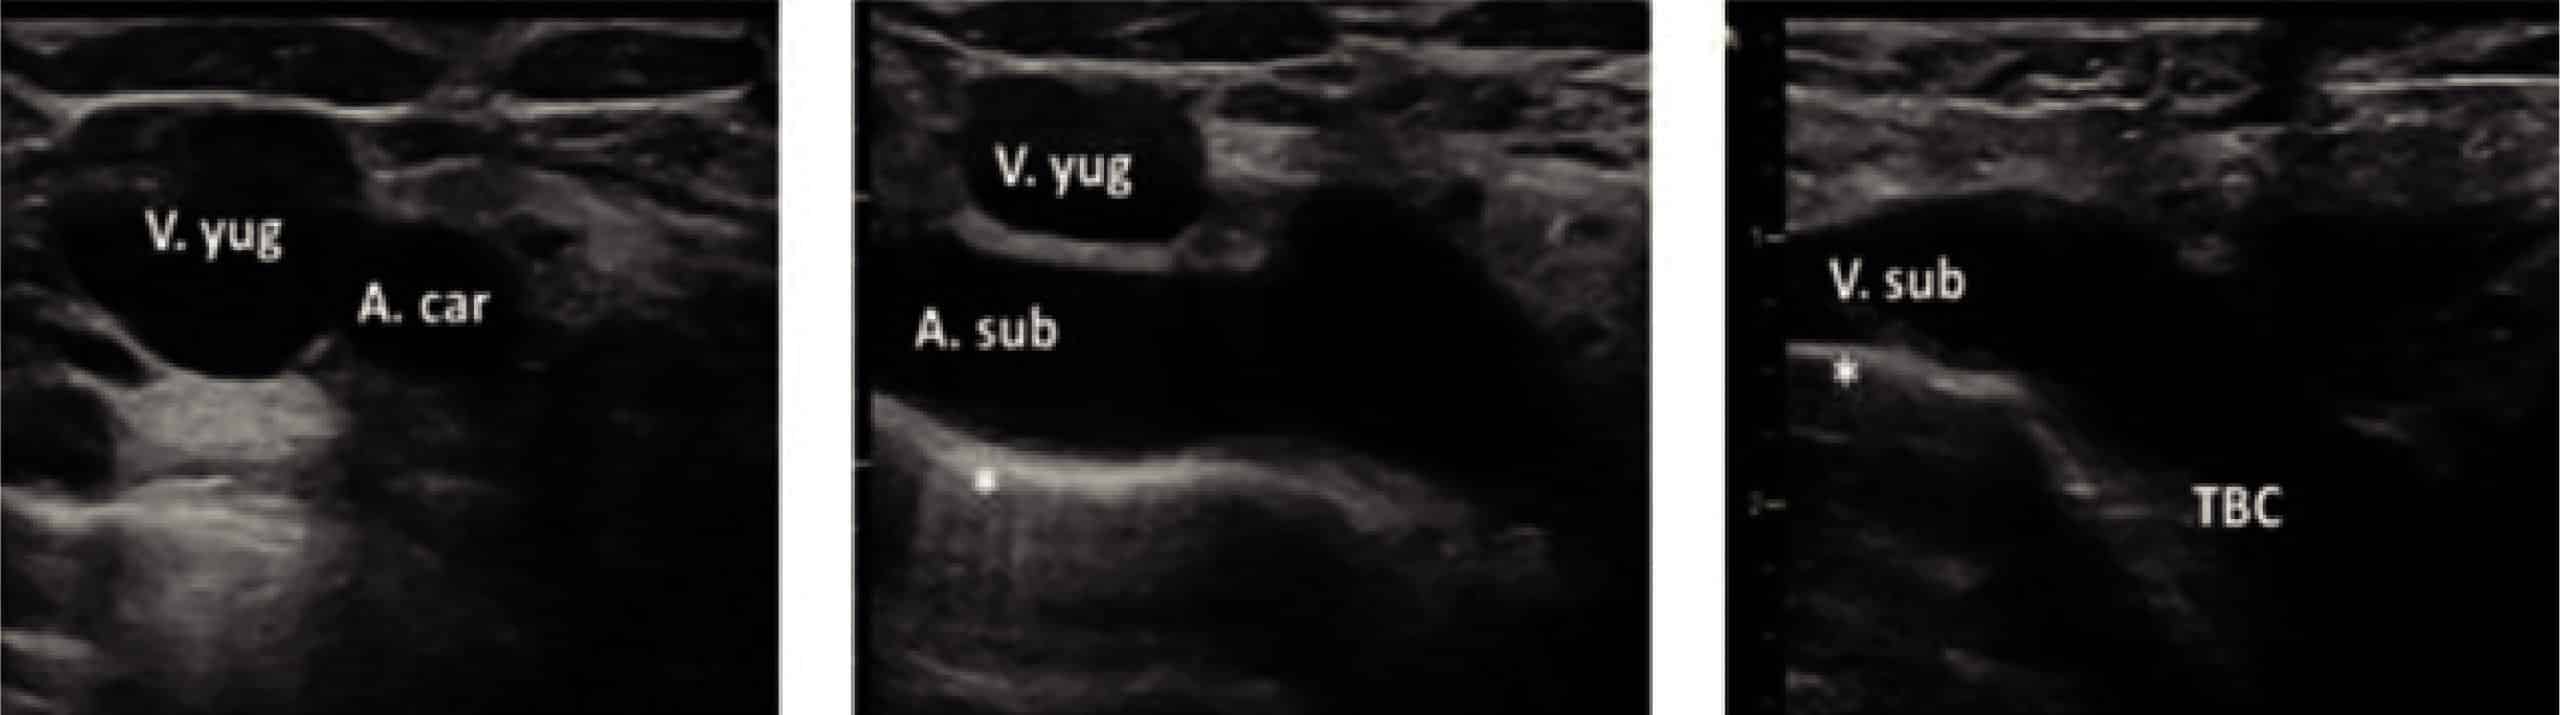

La complicación más común de la canalización es la punción accidental de la arteria carótida. Con un examen de prepunción de ultrasonidos (US), la relación anatómica entre la vena y la arteria puede ser investigada para conseguir el mejor plano con la presentación laterolateral de las estructuras y no anteroposterior y, de esta forma, observar el largo de su longitud antes de decidir el mejor punto de perforación. Esto es esencial debido a las posibles variaciones en las relaciones anatómicas.

Además, hay que tener en cuenta que la relación posicional de los vasos, la cual variará según la posición de la cabeza y del cuello.

- Colocaremos la sonda lineal de alta frecuencia ya lubricada perpendicular al cuello, a nivel del vértice del triángulo formado por: esternocleidomastoideo, la clavícula y la línea que une la apófisis mastoides con el manubrio esternal; con la muesca apuntando a las 21:00 h. aproximadamente. Desde esta posición iremos deslizando la sonda en dirección caudal hasta localizar la posición más idónea para la canalización. En el caso de los niños cuanto más proximal a la clavícula más solapada se encuentra la vena a la carótida; esto aumenta el riesgo de punción arterial incidental.

En líneas generales la vena yugular derecha posee más calibre y además desemboca directamente hacia la cava superior por lo que se considera la lateralidad preferente a la hora de canalizarla.